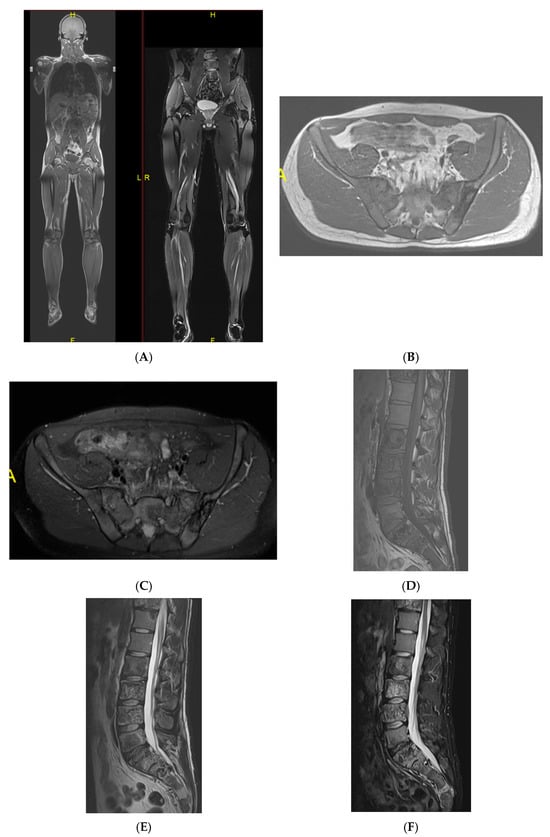

Figure 8.

Multiple haemangiomas. (A) Coronal T1W MRI whole body with side-by-side coronal STIR MRI whole body showing multiple haemangiomas at the vertebral column, pelvis, and proximal femora. (B) Axial T1W Pelvis MRI and (C) STIR Pelvis MRI, further detailing the pelvis lesions. (D) Sagittal T1W Spine MRI with spine haemangiomas. (E) Sagittal T2W Spine MRI with spine haemangiomas. (F) Sagittal STIR Spine MRI with spine haemangiomas. (G) Plain radiograph, pelvis. (H) Plain radiograph, lumbar spine. (I) Plain radiograph, left shoulder. (J) Plain radiograph, right shoulder. All radiographs showcase the corresponding appearances of the lesion on plain films. (K) Axial CT pelvis with biopsy-proven haemangioma at the right hemi-pelvis.